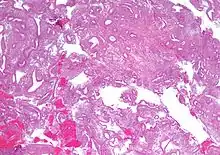

Histopathology of complex hyperplasia without atypia: Cystically dilated endometrial glands lined by a single layer of columnar epithelium.[1]

• Endometrial hyperplasia (simple or complex) - Irregularity and cystic expansion of glands (simple) or crowding and budding of glands (complex) without worrisome changes in the appearance of individual gland cells. In one study, 1.6% of patients diagnosed with these abnormalities eventually developed endometrial cancer.[6]